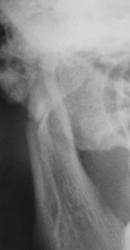

Замечания: не маркирована сторона, не достаточно косой снимок - наложение сторон. Стоило снять с двух сторон.

Владимир Борисович, спасибо, учтем. Просто ургентируют разные лаборанты - одни более ответственны, другие менее.